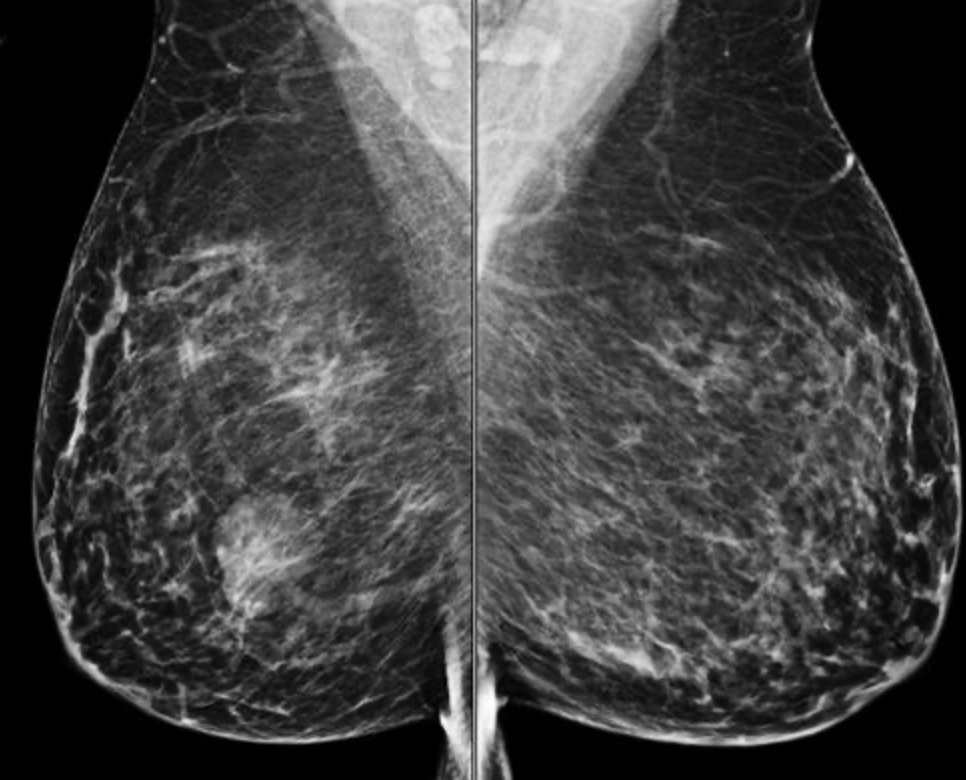

Imaging: bilateral MLO and CC views of the breasts. There is an ovoid mass in the right lower, outer quadrant.

- On mammography:

- The most common appearance described is:

- A well-defined, uncalcified mass, with regular borders

- Spiculated borders, suspicious borders, and architectural distortion can also be seen:

- But are uncommon